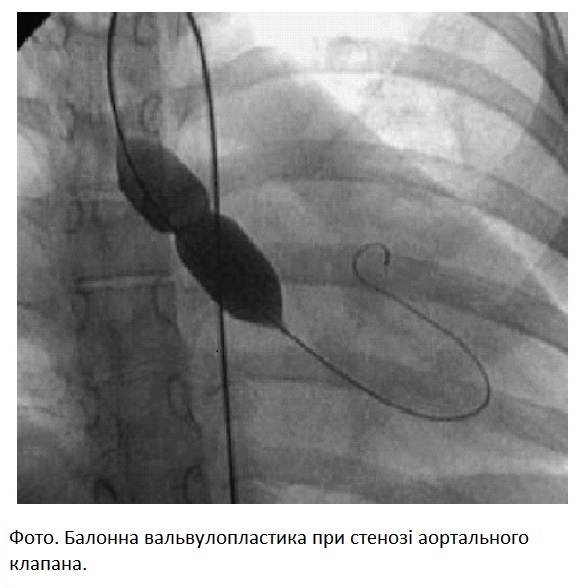

Під час вагітності широко застосовують малоінвазивні черезшкірні ендоваскулярні втручання:

-